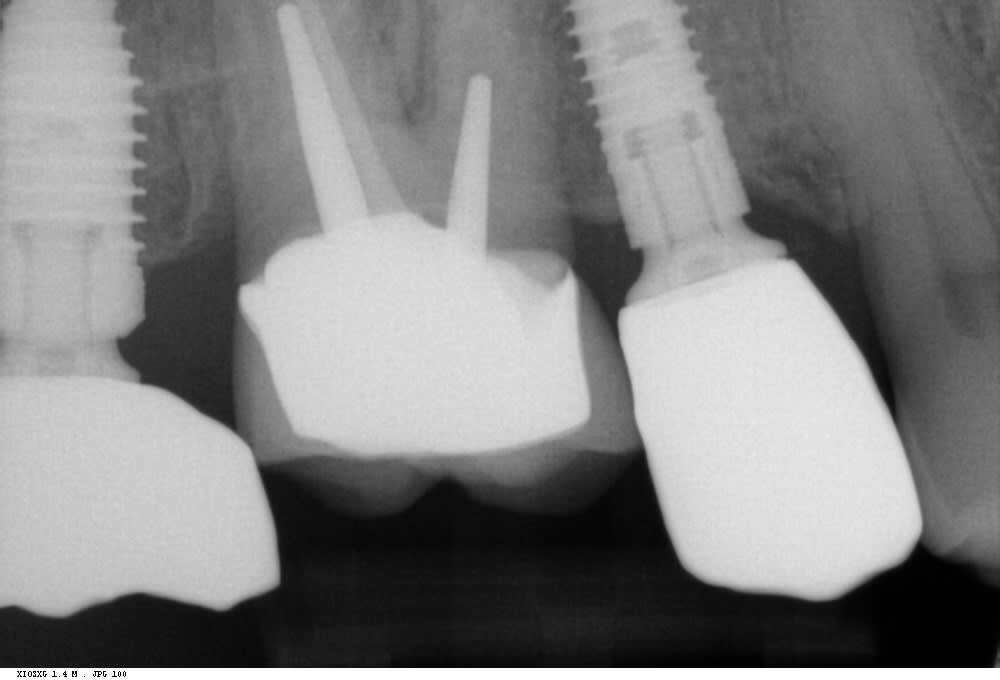

- le niveau osseux autour de la 6 , il est impeccable

- l adaptation cervicale , au top . si entre 2 pts de contacts implantaire les pts étaient trop serré , ce ne serait pas le cas

- la dent devait etre devitalisée depuis longtemps en tout cas bien plus de 6 mois , elle parait collée à l os .

- la racine mesiale est coube , la furcation en pleine forme , os dense , comment veux tu que ça bouge ?

Rien de particulier de noté au cbct fait par mon correspondant implanto. je vais lui demander les coupes

Si les points de contact sont serrés, je ne comprends même pas comment la couronne a pu être mise en place: nous sommes au-delà de la ligne de plus grand contour!

Je rappelle que les deux adjacents sont sur implant, impossible de jouer sur le ligament popur passer en force.

J'ai une théorie, je ne sais pas si elle est crédible du point de vue scientifique: peut-on considérer une certaine souplesse de l'os au niveau de la tubérosité, qui aurait justement permis cette insertion en force? De l'os, ou du corps de l'implant, qui aurait ensuite agi comme un appareillage odf en tentant de revenir en position intiale, donc en poussant la 6 en direction mésiale et apicale, le mésial étant bloqué par l'implant 5?